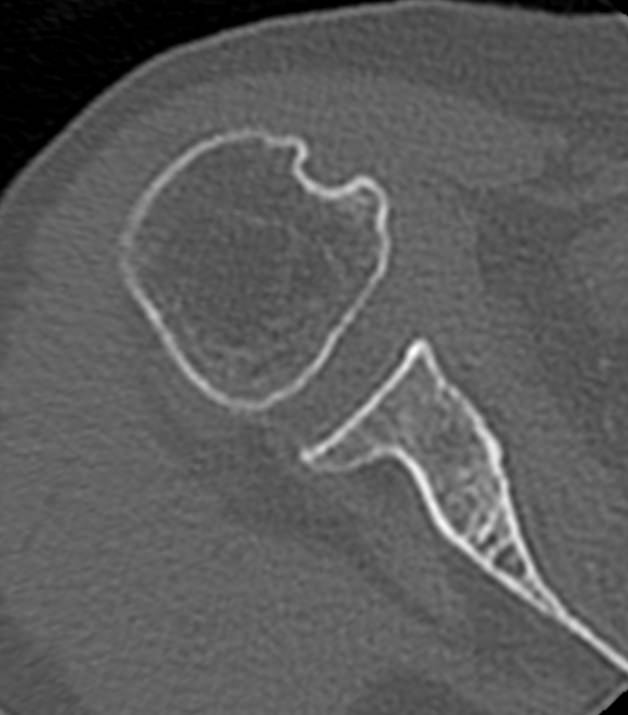

Так как рентгеновские лучи хорошо поглощается костной тканью, метод КТ наиболее информативен именно для обследования костных структур. Кроме того, компьютерная томография отличается быстротой, безболезненностью и неинвазивностью (то есть не требует вмешательства в организм человека). Поэтому методика, в первую очередь, применяется для диагностики травматических повреждений – различных переломов, вывихов и подвывихов плечевого сустава.

В случае необходимости проведения оперативного вмешательства КТ дает исчерпывающую информацию о расположении костных отломков, а после операции позволяет оценить правильность репозиции фрагментов кости и состояние эндопротеза.

- Что показывает КТ плечевого сустава

Что показывает КТ плечевого сустава

- трещины, переломы (в т. ч. скрытые),образовавшиеся в полости сустава или в прилегающих тканях гематомы;